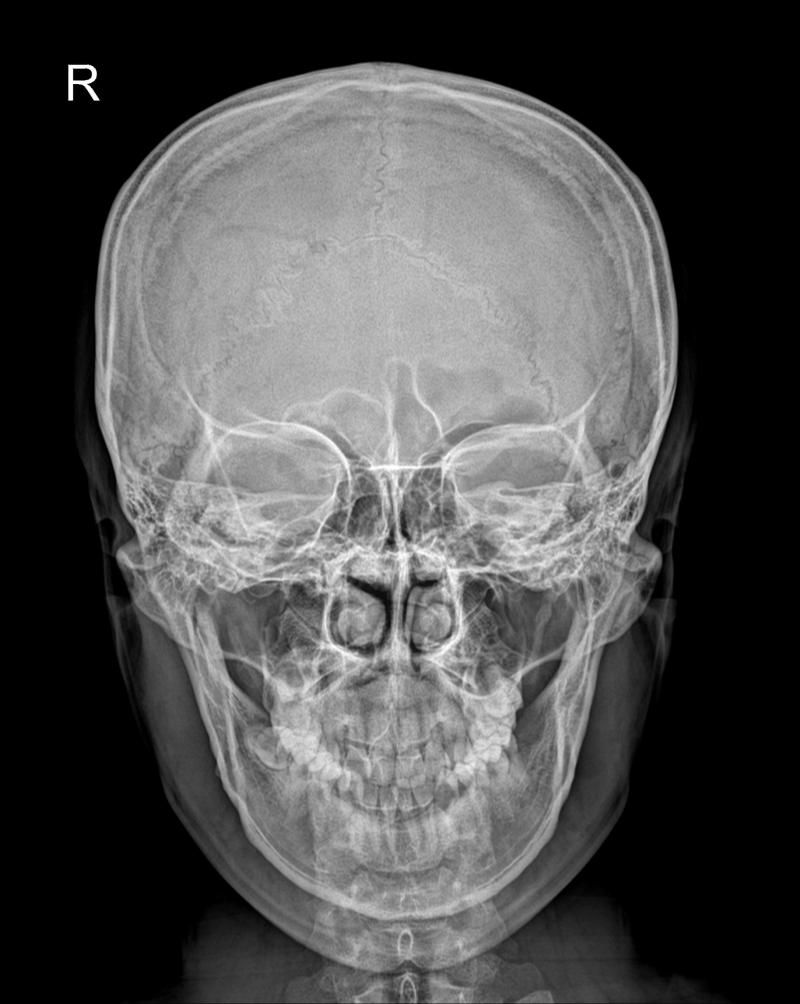

두 두개골 x레이 차이를 알려주세요.

두번째 이미지가 비대칭이 더 심해보이는데

정확히 어떤 부분이 변했나요?

그리고 턱이 왼쪽으로 기울어진 것 맞나요?

첫 번째 이미지가 좀 더 좋아보입니다.

아래턱뼈에 붙어있는 아래 어금니를 보시면 양쪽 윗 어금니와 간격이 일정해보이지만,

두 번째 이미지는 아래턱뼈가 좀 정렬이 안맞는 것 같습니다.

X-ray상 두 번째 이미지에 아래턱뼈가 좌측으로 휘어있습니다.

음영조절이나 색상반전을 해보시면 두 번째 이미지에 턱 부분의 실루엣이 좌측으로 넘어가 있을겁니다.